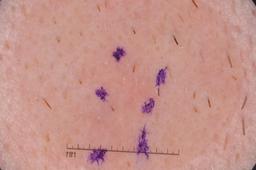

MSK-4

- Name: MSK-4

Description:

Images found based on a search for patients with a personal history, clinical diagnosis, or differential diagnosis of melanoma. All diagnoses confirmed by histopathology.